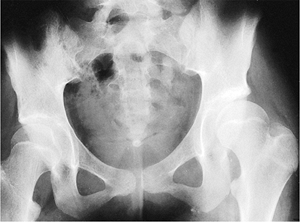

patients with Duchenne muscular dystrophy and found that 15 had

unilateral subluxation, 1 had bilateral subluxation, and 3 had a

unilateral dislocation. They recommended serial pelvic radiographs in

patients with this disorder. They also felt that any pelvic obliquity

should be corrected at the time of spinal stabilization.